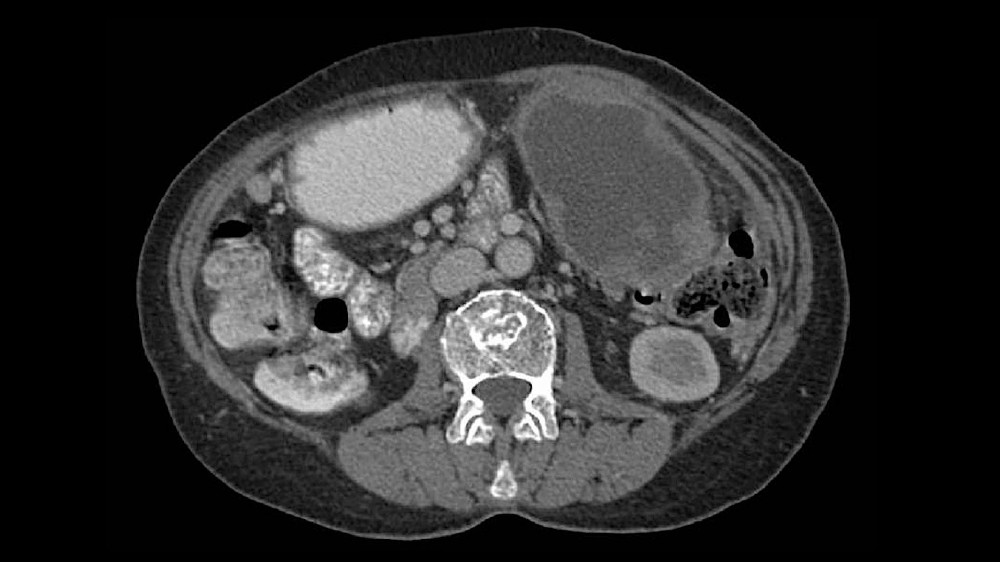

腹圍增加或腹水(液體積聚)造成腫脹

因大量腹水而導致嚴重且明顯的腹部腫脹

由於腹膜廣泛擴散,腹水形成變得突出